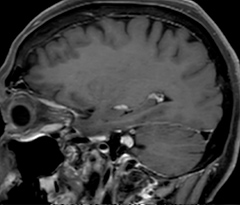

A two year follow-up scan of a CPA meningioma using both Ingenia 3.0T without CS and Ingenia Elition 3.0T with Compressed SENSE allows for a nice comparison to demonstrate the protocol improvements achieved on the Elition: 3D FLAIR has a shortened scan time, improved SNR and still the same spatial resolution. BrainView (3D T1 TSE) has improved spatial resolution and SNR with shortened scan time. For 3D T2 Drive the spatial resolution has been improved. 3D THRIVE used to have an interpolated 0.8 mm slice thickness, but true thickness at 1.6 mm, so that axial slices displayed a decent quality, but reformats were suboptimal.

Compressed SENSE is used on Elition to improve spatial resolution and reduce the non-interpolated slice thickness to allow smoothly reformatted images. Total scan time (adding SmartBrain and an additional b2000 diffusion) was 13:19 on Ingenia, and is now reduced to 10:42 on Ingenia Elition.

Ingenia 3.0T (without Compressed SENSE)

3D FLAIR (without Compressed SENSE)

3D FLAIR

1.0 x 1.0 x 1.0 mm*

4:24 min.

3D TSE T1w (without Compressed SENSE)

3D TSE T1w

1.0 x 1.0 x 1.2 mm*

2:40 min.

3D T2w Drive (without Compressed SENSE)

3D T2w Drive

0.8 x 0.8 x 1.0 mm*

3:05 min.

3D T1w THRIVE (without Compressed SENSE)

3D T1w THRIVE

0.8 x 0.8 x 1.6 mm*

1:30 min.

Ingenia Elition 3.0T with Compressed SENSE

3D FLAIR (with Compressed SENSE)

2:50 min.

3D TSE T1w (with Compressed SENSE)

2:10 min.

3D T2w Drive (with Compressed SENSE)

0.7 x 0.7 x 0.7 mm*

2:52 min.

3D T1w THRIVE (with Compressed SENSE)

0.7 x 0.7 x 0.8 mm*

*true voxel size, without interpolation